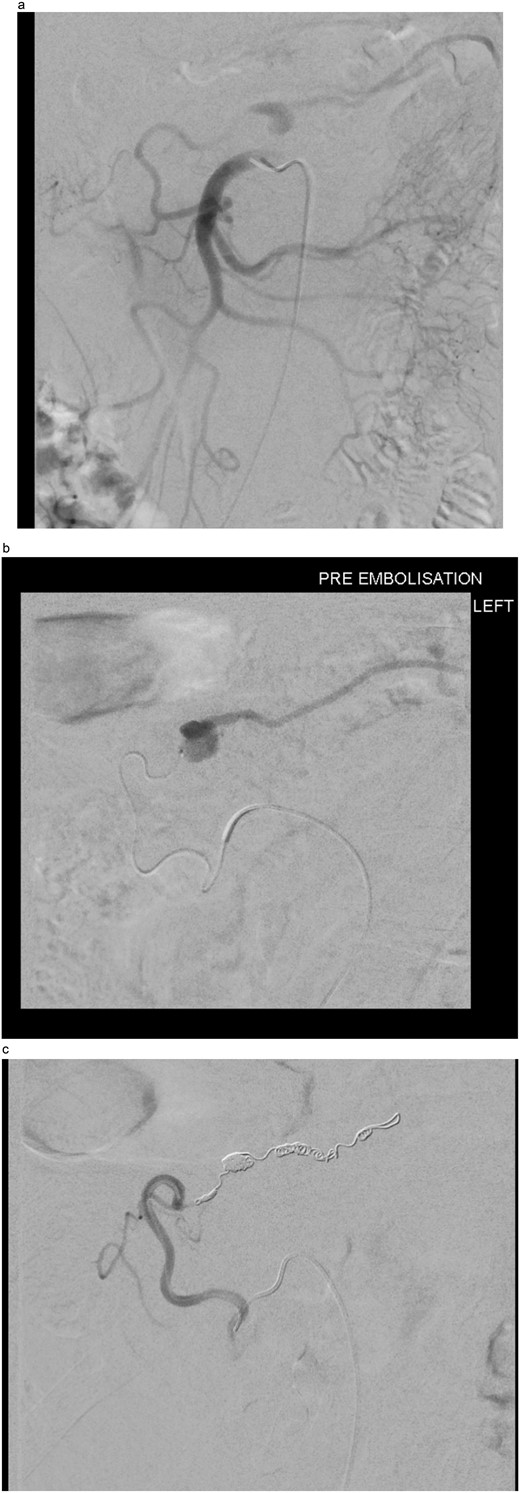

On day five post-operatively, the patient deteriorated, developing hypotension, diaphoresis, a new oxygen requirement, and complaining of new onset back pain. This is in conjunction with a drop in haemoglobin (Hb) from 129 g/L (day one post-operatively) to 89 g/L on Day 5. An abdominal CT Angiogram was performed, showing a pseudoaneurysm of the Marginal artery of Drummond measuring 1.2 × 1 × 1 cm (AP × TR × CC) with some surrounding haematoma in the small bowel mesentery (see Fig. 1). Following multi-disciplinary team (MDT) discussion, three possible management options arose: observe and re-scan the following day and optimize Hb, embolize the artery (although this has a risk of bowel infarction) or to resect the bowel. We decided to adopt a watch-and-wait approach and repeat the CTA the following day, which showed no significant change in the pseudoaneurysm. He was discharged home on Day 6 post-operatively.

CT angiogram performed on 5th postoperative day, demonstrating a small false aneurysm (1.2 × 1 × 1 cm) arising from the marginal artery of Drummond.